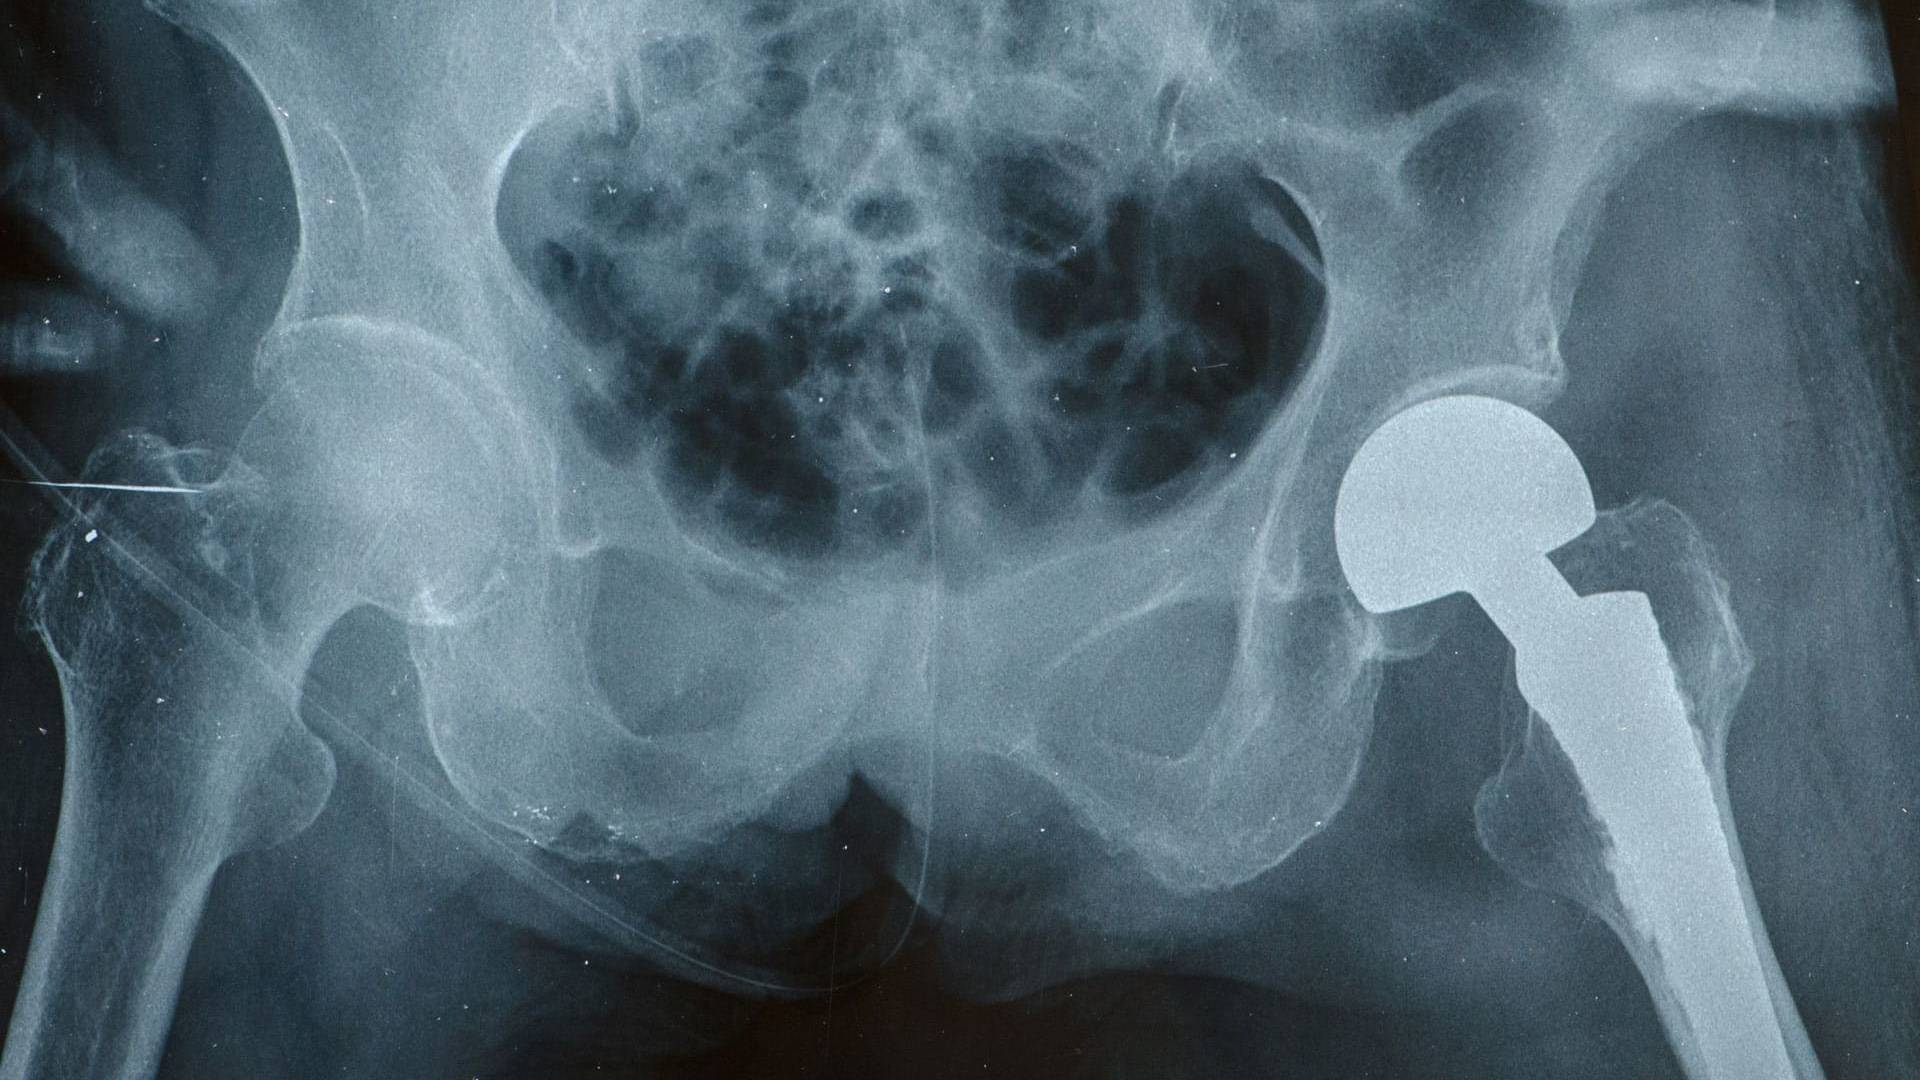

Béquille, paire de lunettes, prothèse de hanche, implant dentaire, préservatif, pansement… Les dispositifs médicaux (DM) s’avèrent particulièrement difficiles à caractériser en raison de leur extrême diversité !

Au sein de cette classification, les produits situés à la frontière entre médicament et dispositif médical sont nombreux. A titre d’exemple, une seringue pré-remplie d’une substance médicamenteuse est considérée comme un médicament tandis que vide, elle devient un dispositif médical. D’une manière générale, qu’il s’agisse d’implants mammaires, de prothèses articulaires, de pansements, de fauteuils roulants… la classification des dispositifs médicaux se réfère à leur niveau de dangerosité.